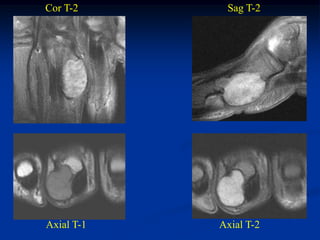

Cor T-2      Sag T-2

Axial T-1   Axial T-2